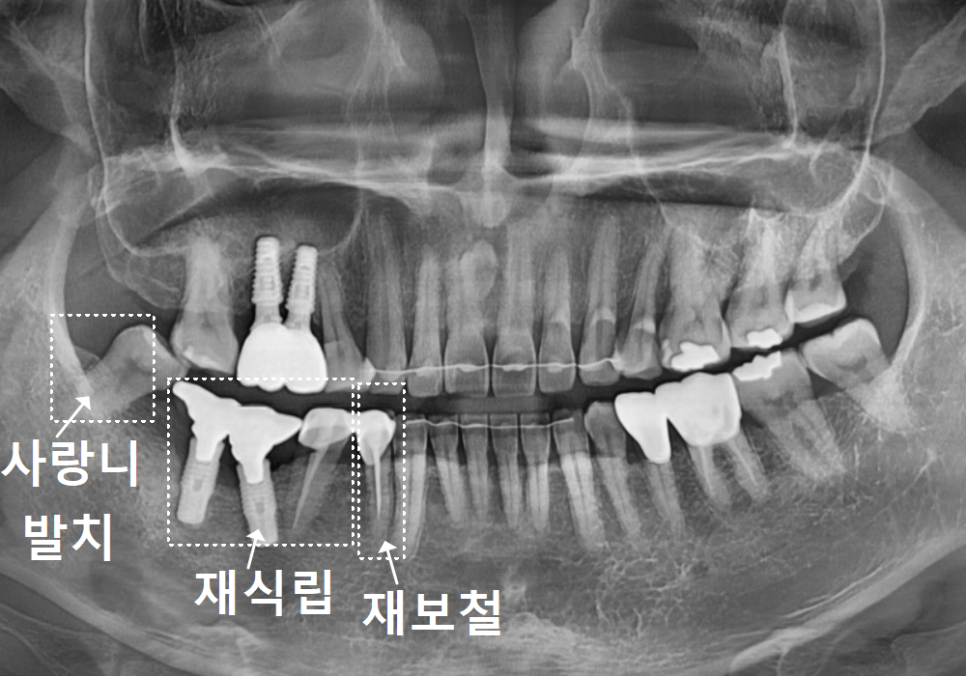

정밀 사진을 보니

어금니 쪽 임플란트(#46, 47) 주변 잇몸뼈가

251118

염증(임플란트 주위염) 때문에

많이 녹아 있는 상태였는데요.

특히 CT로 분석해 보니 임플란트를

양옆에서 꽉 잡아줘야 할 뼈 중

한쪽 면이 염증으로 완전히 소실되어 있었죠.

게다가 뒤쪽에 있는 사랑니까지

염증을 더 악화시키고 있었습니다.

더 안타까운 건 주변 치아들의 상태였어요.

임플란트 옆에 도자기로 씌워둔 치아(#45)의

보철물이 깨져 있었는데,

그 틈으로 음식물이 계속 끼어 들어가면서

치아 뿌리 깊숙이 충치가 생긴 상태였어요.

우선 염증의 원인인 사랑니와

이미 뼈가 녹아버린 임플란트들은

발치가 불가피했습니다.